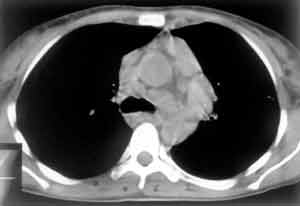

Рис. 5. Трахеобронхиальные и бифуркационные лимфатические узлы.